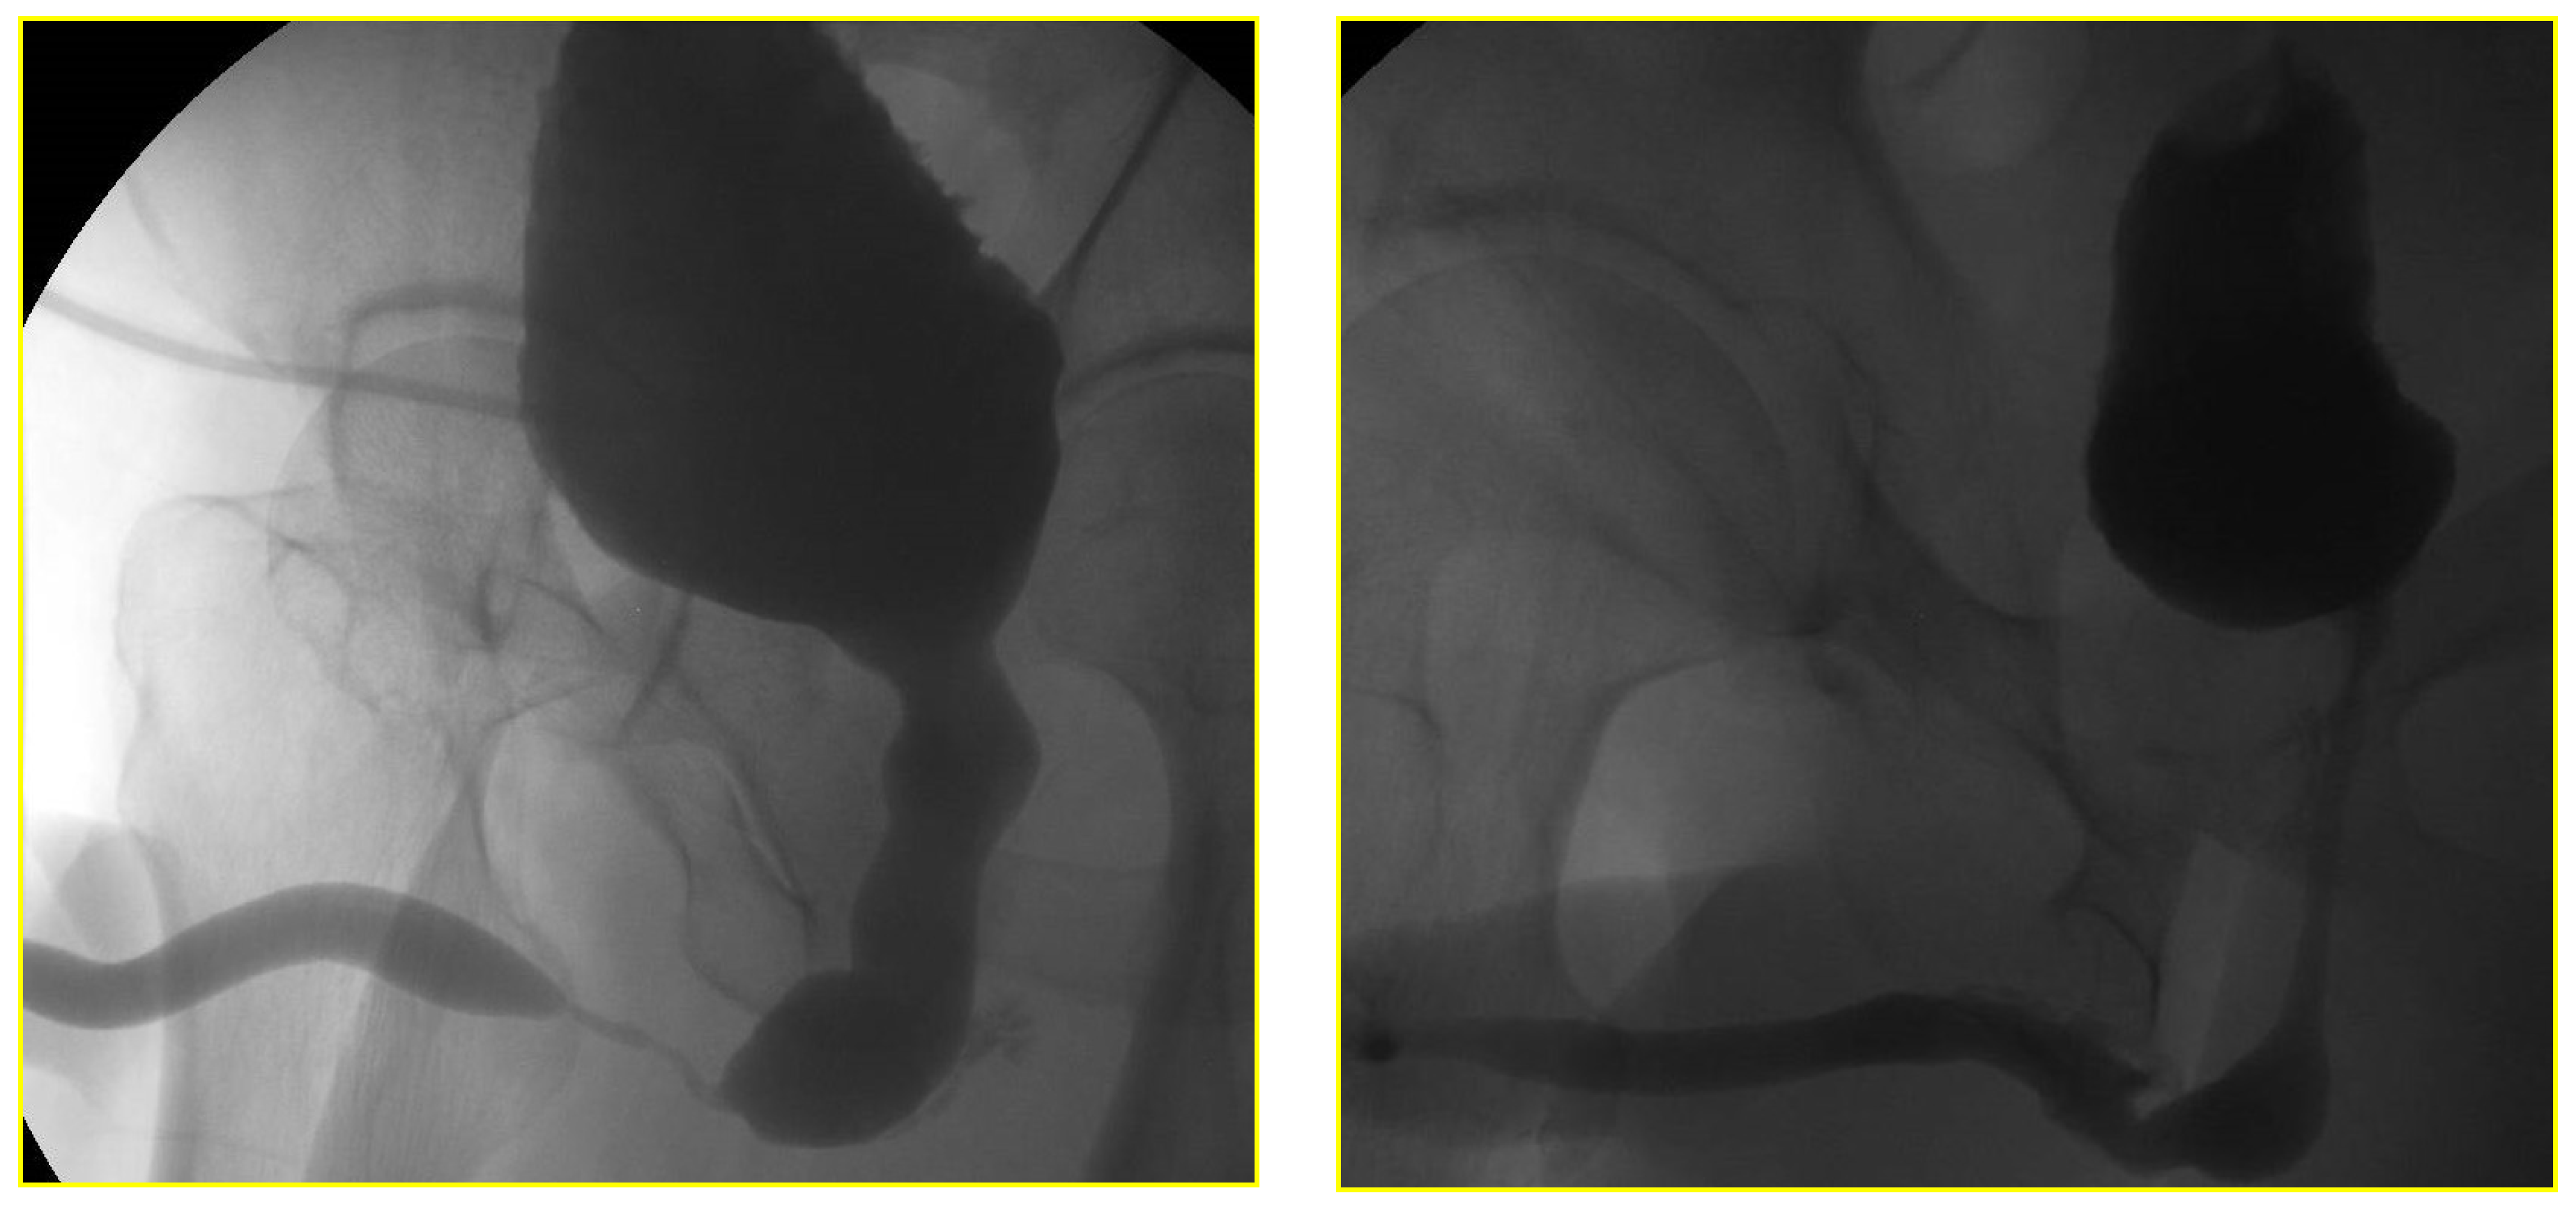

The RGU performed at the time of catheter removal of patients in Group 1 on day one demonstrated minimal extravasation but no voiding difficulty in six patients (32%). These patients were discharged from the hospital without reinserting a Foley catheter. The extravasation cleared up spontaneously when the patients had a follow-up RGU six weeks after catheter removal (Figure 4 and Figure 5). The patients with minimal extravasation did not develop any clinical problems. The patients in Group 2 had their urethral catheters removed two weeks post-surgery, and an RGU was performed six weeks after catheter removal. Stricture recurrence occurred in Group 1 at 3.6 and 6.2 months. The seven failures in Group 2 occurred at an average of 5.6 months (range 1.1 to 10.1) (p = 0.804).

Figure 5. Retrograde urethrogram in a patient with 0.8 cm stricture pre and 24-h post double-layer continuous running suture re-anastomosis.